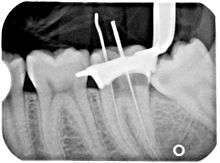

x-ray of a root canal operation

Another common complication of root canal therapy is when the entire length of the root canal is not completely cleaned out and filled (obturated) with root canal filling material (usually gutta percha). The X-ray in the right margin below shows two adjacent teeth that had received bad root canal therapy. The root canal filling material (3, 4 & 10) does not extend to the end of the tooth roots (5, 6 & 11). The dark circles at the bottom of the tooth roots (7 & 8) indicated infection in the surrounding bone. Recommended treatment is either to redo the root canal therapy if possible or extract the tooth and place dental implant(s). [31]

An X-ray explanation of bad root canal therapy

An X-ray explanation of bad root canal therapy. See text above.